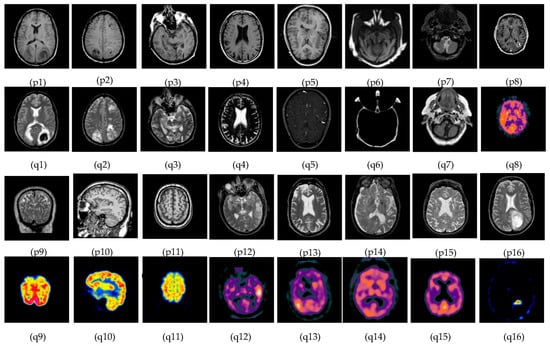

The subjective evolution is carried out on various input datasets as shown in Figure 3. In this paper, five groups of datasets have been used. The group 1 input images are MR-T1–MR-T2 datasets as shown in Figure 3((p1–p4) and (q1–q4)). Group 2 input images are MR-T1 and MRA as shown in Figure 3((p5) and (q5)). Group 3 input images are MRI and CT in Figure 3((p6–p7) and (q6–q7)), and group 4 input data set images are MRI and PET in Figure 3((p8–p11) and (q8–q11)). Finally, group 5 input images are MR-T2 and SPECT datasets as shown in Figure 3((p12–p16) and (q12–q16)). In this article, the performance of the proposed fusion scheme is compared with various existing algorithms, namely, the PCA method, Naidu’s [52] method, Sanjay’s [29] method, contourlet transform (CONT) method, Chaira’s IFS [53] method, Bala’s IFS [54] method, Sugeno’s IFS [55] method, and Zhu’s [56] method are in Figure 4. The fusion results of the PCA method-based fusion images are shown in the first column in Figure 4(a1–a16), DWTPCA method-based fusion images are displayed in the second column in Figure 4(b1–b16), DWT with fuzzy method-based fusion images are shown in the third column in Figure 4(c1–c16), CONT method based fusion images are displayed in the fourth column in Figure 4(d1–d16), Chaira’s IFS-method based fusion images are shown in the fifth column in Figure 4(e1–e16), Bala’s IFS method based fusion images are displayed in the sixth column in Figure 4(f1–f16), Sugeno’s IFS-method based fusion images in the seventh column in Figure 4(g1–g16), PC- NSCT method based fusion images are in the eighth column in Figure 4(h1–h16). Finally, the proposed fusion images are exhibited in the last column in Figure 4(i1–i16). Subjective analysis is related to human perception, and the proposed fusion method proves, the fused image has greater contrast, luminance, and better edge information than other existing methods, and clear tumor regions are shown in Figure 4((i4), (i8), (i12), (i13), and (i16)).

Figure 3.

Medical image datasets: (p1–p4) and (q1–q4) are MR T1–MR T2 input images: (p5) and (q5) are T1 weighted MR–MRA input images; (p6,p7) and (q6,q7) are MRI–CT input images; (p8–p11) and (q8–q11) are MRI–PET input images; and (p12–p16) and (q12–q16) are the MR-T2–SPECT input images.

The proposed fusion results show that the quality of the fused image is better than other existing fusion methods. Among all the groups of medical image datasets, the first group of medical image datasets are T1–T2 weighted MR images. Fusing these two images shows soft tissue and an enhanced tumor region. The second group of medical image datasets are MR-T1and MRA images. MR-T1 images produce delicate tissue data but do not detect the abnormalities in the image, while the MRA image easily detects the abnormalities but due to low spatial resolution, is unable to produce the tissue information. Fusion of these images (MR-T1 and MRA) shows the complementary information with detailed lesion locations in the fused image.

The third group dataset consists of MRI and CT images, which are taken from reference [44]. MRI imaging produces delicate tissue data, while CT imaging gives bone information. The combination of these two images produces a quality fused image, which will be more useful for the diagnosis of disease. The fourth and fifth medical image datasets are MRI–PET and MR-T2–SPECT images. The fusion of these combinations to get more complementary information is achieved in a fused image and highlights the tumor regions, which will be helpful for medical-related problems.